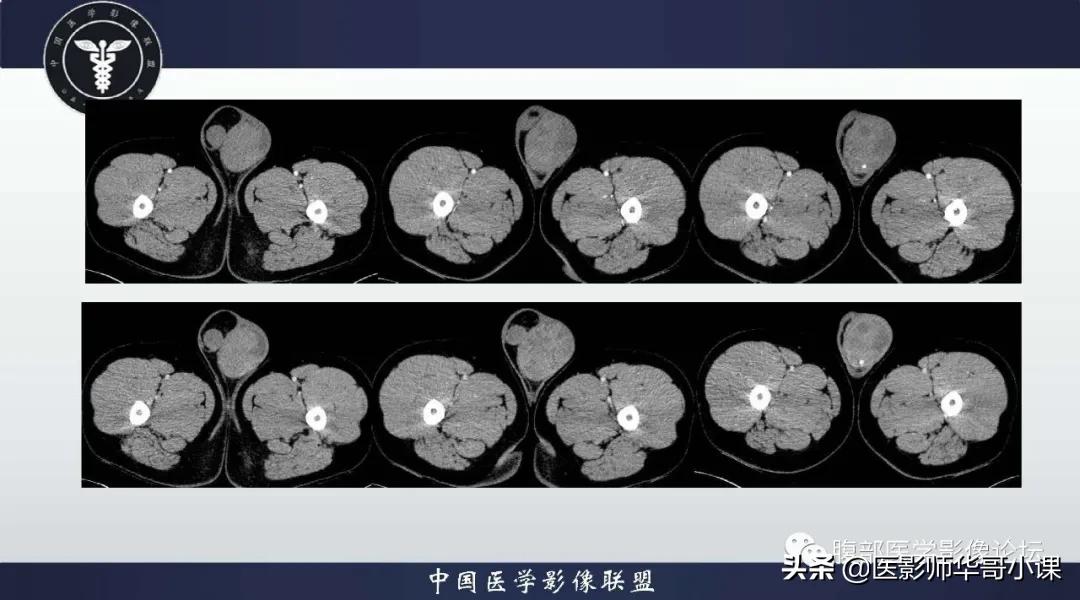

影像学表现与病理相符合,MRI显示肿块呈多发结节状,T1WI 呈等信号,与正常*丸睾**T1WI 信号相等,T2WI 信号低于正常*丸睾**组织, 瘤内纤维血管分隔数量不等,粗细不均,增强扫描纤维血管分隔强化高于肿瘤组织 。由于肿块浸润受到白膜限制,其轮廓一般清楚。大部分文献报道精原细胞瘤较少出现坏死、出血。